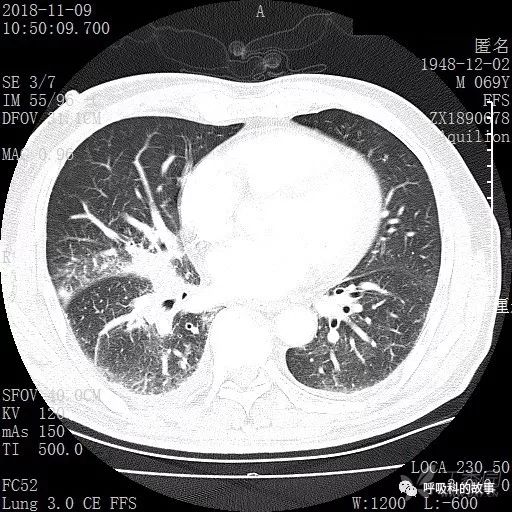

胸部增强CT示右肺门占位伴远端阻塞性肺炎,纵膈、右肺门、右侧颈根部、右侧腋下及肝门部肿大淋巴结。两侧胸腔少量积液。

肺窗CT